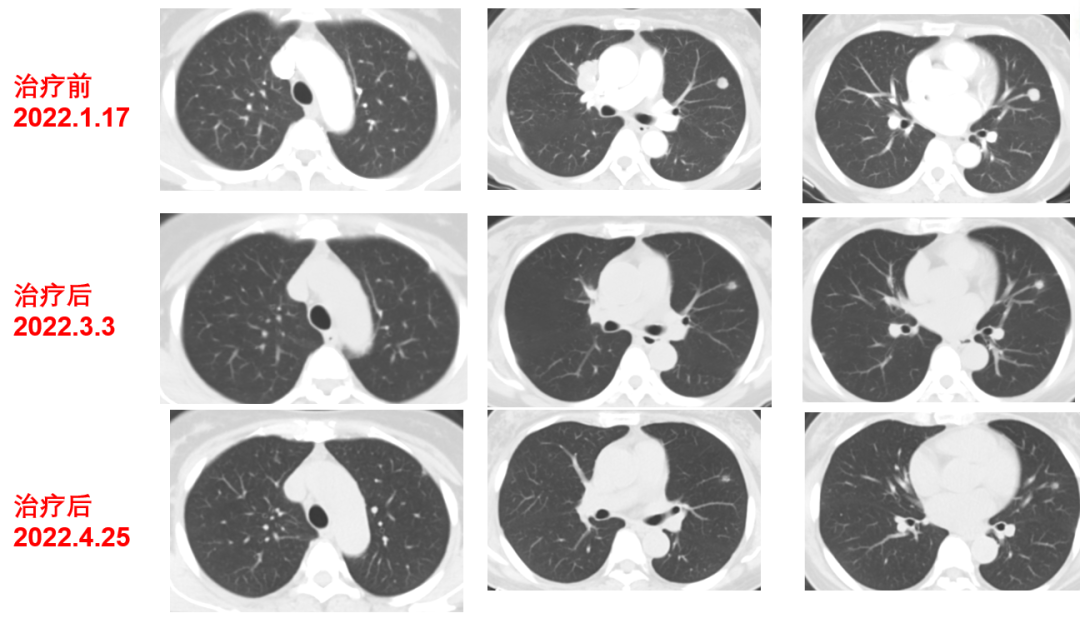

于2021-12-03、2021-12-27给予伊尼妥单抗+吡咯替尼方案治疗2周期。2022.1.19始给予患者伊尼妥单抗+吡咯替尼+替雷利珠单抗治疗,两周期,四周期时的疗效评估可以看到,肺上病灶明显缩小,甚至有的病灶消失,肿瘤标志物也在持续下降。

肿瘤第二次进展(2022-8-3):在二线治疗7月余后,肿瘤标志物升高,CT也显示,肺上的病灶增大,患者双靶向+免疫治疗进展。